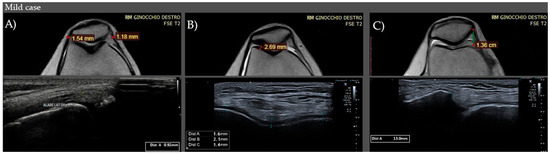

| CONTROLS | Medial Retinaculum | 0.9–1.0 mm (IQR) (M1) | 0.9–1.1 mm (IQR) (M1) |

| Lateral Retinaculum | 0.7–1.0 mm (IQR) (M0.9) | 0.9–1 mm (IQR) (M1) | |

| CASES | Medial Retinaculum | 1.3–2.6 (IQR) (M2.1) Mild: <1.3 mm Moderate: 1.3–2.6 mm Severe: >2.6 mm | 1.5–2.8 (IQR) (M2.3) Mild: <1.5 mm Moderate: 1.5–2.8 mm Severe: >2.8 mm |

| Lateral Retinaculum | 1.2–2.5 (IQR) (M0.9) Mild: <1.2 mm Moderate: 1.2–2.5 mm Severe: >2.5 mm | 1.3–2.5 (IQR) (M2.2) Mild: <1.3 mm Moderate: 1.3–2.5 mm Severe: >2.5 mm | |

| CONTROLS | Medial Thickness | 2.8–4.7 mm (IQR) (M4) | 2.9–4.5 mm (IQR) (M3.8) |

| Lateral Thickness | 3.3–5.1 mm (IQR) (M4.45) | 3.0–4.8 mm (IQR) (M4.2) | |

| CASES | Medial Thickness | 1.5–2.3 (IQR) (M1.8) Mild: >2.3 mm Moderate: 1.5–2.3 mm Severe: <1.5 mm | 1.2–2.1 (IQR) (M1.55) Mild: >2.1 mm Moderate: 1.2–2.1 mm Severe: <1.2 mm |

| Lateral Thickness | 1.8–2.65 (IQR) (M2.3) Mild: >2.6 mm Moderate: 1.8–2.6 mm Severe: <1.8 mm | 1.65–2.5 (IQR) (M2) Mild: >2.5 mm Moderate: 1.6–2.5 mm Severe: <1.6 mm | |